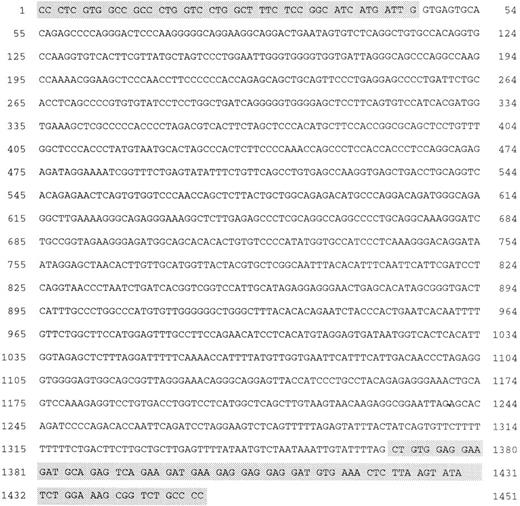

Standard DNA-PCR allowed the detection of amplicons (0.6 to 2.2 kb) by gel staining in 3 CD30+ secondary CTCL (cases no. 1, 2, and 3) and in 1 CD30+ primary CTCL (case no. 8; Fig 5). These cases (no. 1, 2, 3, and 8) were also positive at the DNA-PCR level on derivative chromosome 5 and by both standard and nested RT-PCR analysis. Size-specific amplicons were also obtained by nested DNA-PCR for cases no. 2, 3, and 8 but not for case no. 1. Titration study showed that the sensitivity of this DNA-PCR was 10−2 for the standard PCR and 10−3 for the nested PCR (results not shown). Southern blot hybridization with both NPM-2P and ALK-2P confirmed these results in 3 of the 4 cases. In case no. 1 (CD30+ secondary CTCL), a positive hybridization of standard PCR products, was obtained only with NPM-2P, but not with ALK-2P. Sequence analysis showed that the standard DNA-PCR amplicon of case no. 1 contained the 3′ end of the NPM exon targeted by the 3′NPM2int oligonucleotide and the flanking intron, but lacked the 5′ end of the ALK exon targeted by the 5′ALK2int primer. Amplicons of the nested DNA-PCR in cases no. 2, 3, and 8 and the SU-DHL-1 cell line were purified and sequenced (Fig 6). Multiple alignment analysis of these sequences showed a perfect homology of chimeric intronic sequences ranging from both exonic extremities over a variable area from case to case depending on the position of the breakpoint (data not shown). The complete sequence of the reciprocal breakpoint DNA fragment of the SU-DHL1 was characterized (Genbank accession no. AF032882). No genomic breakpoint was amplified in the MF and BID cases.

Amplification of genomic breakpoint on derivative chromosome 2. Genomic DNA was subjected to standard and nested amplification, followed by product separation on a 1% agarose gel. Ethidium bromide staining of standard DNA-PCR products (A) and of the nested DNA-PCR products (D). Lanes 1 through 11, cases 1 through 11; lane 12, t(2;5)+ SU-DHL-1 cell line; lane M, molecular weight marker 1-kb DNA ladder (GIBCO-BRL). The gels were transferred to a nylon membrane and hybridized either with the ALK-2P (radioautographies B and E) or the NPM-2P (radioautographies C and F). The sizes are indicated in bases.

Amplification of genomic breakpoint on derivative chromosome 2. Genomic DNA was subjected to standard and nested amplification, followed by product separation on a 1% agarose gel. Ethidium bromide staining of standard DNA-PCR products (A) and of the nested DNA-PCR products (D). Lanes 1 through 11, cases 1 through 11; lane 12, t(2;5)+ SU-DHL-1 cell line; lane M, molecular weight marker 1-kb DNA ladder (GIBCO-BRL). The gels were transferred to a nylon membrane and hybridized either with the ALK-2P (radioautographies B and E) or the NPM-2P (radioautographies C and F). The sizes are indicated in bases.

Genomic nucleotide sequence of the reciprocal translocation on the derivative chromosome 2 in SU-DHL1. The shaded boxes at the 5′ end and at the 3′ end of the sequence contain, respectively, the ALK exon sequence and the NPM exon sequence flanking the breakpoint.

Genomic nucleotide sequence of the reciprocal translocation on the derivative chromosome 2 in SU-DHL1. The shaded boxes at the 5′ end and at the 3′ end of the sequence contain, respectively, the ALK exon sequence and the NPM exon sequence flanking the breakpoint.